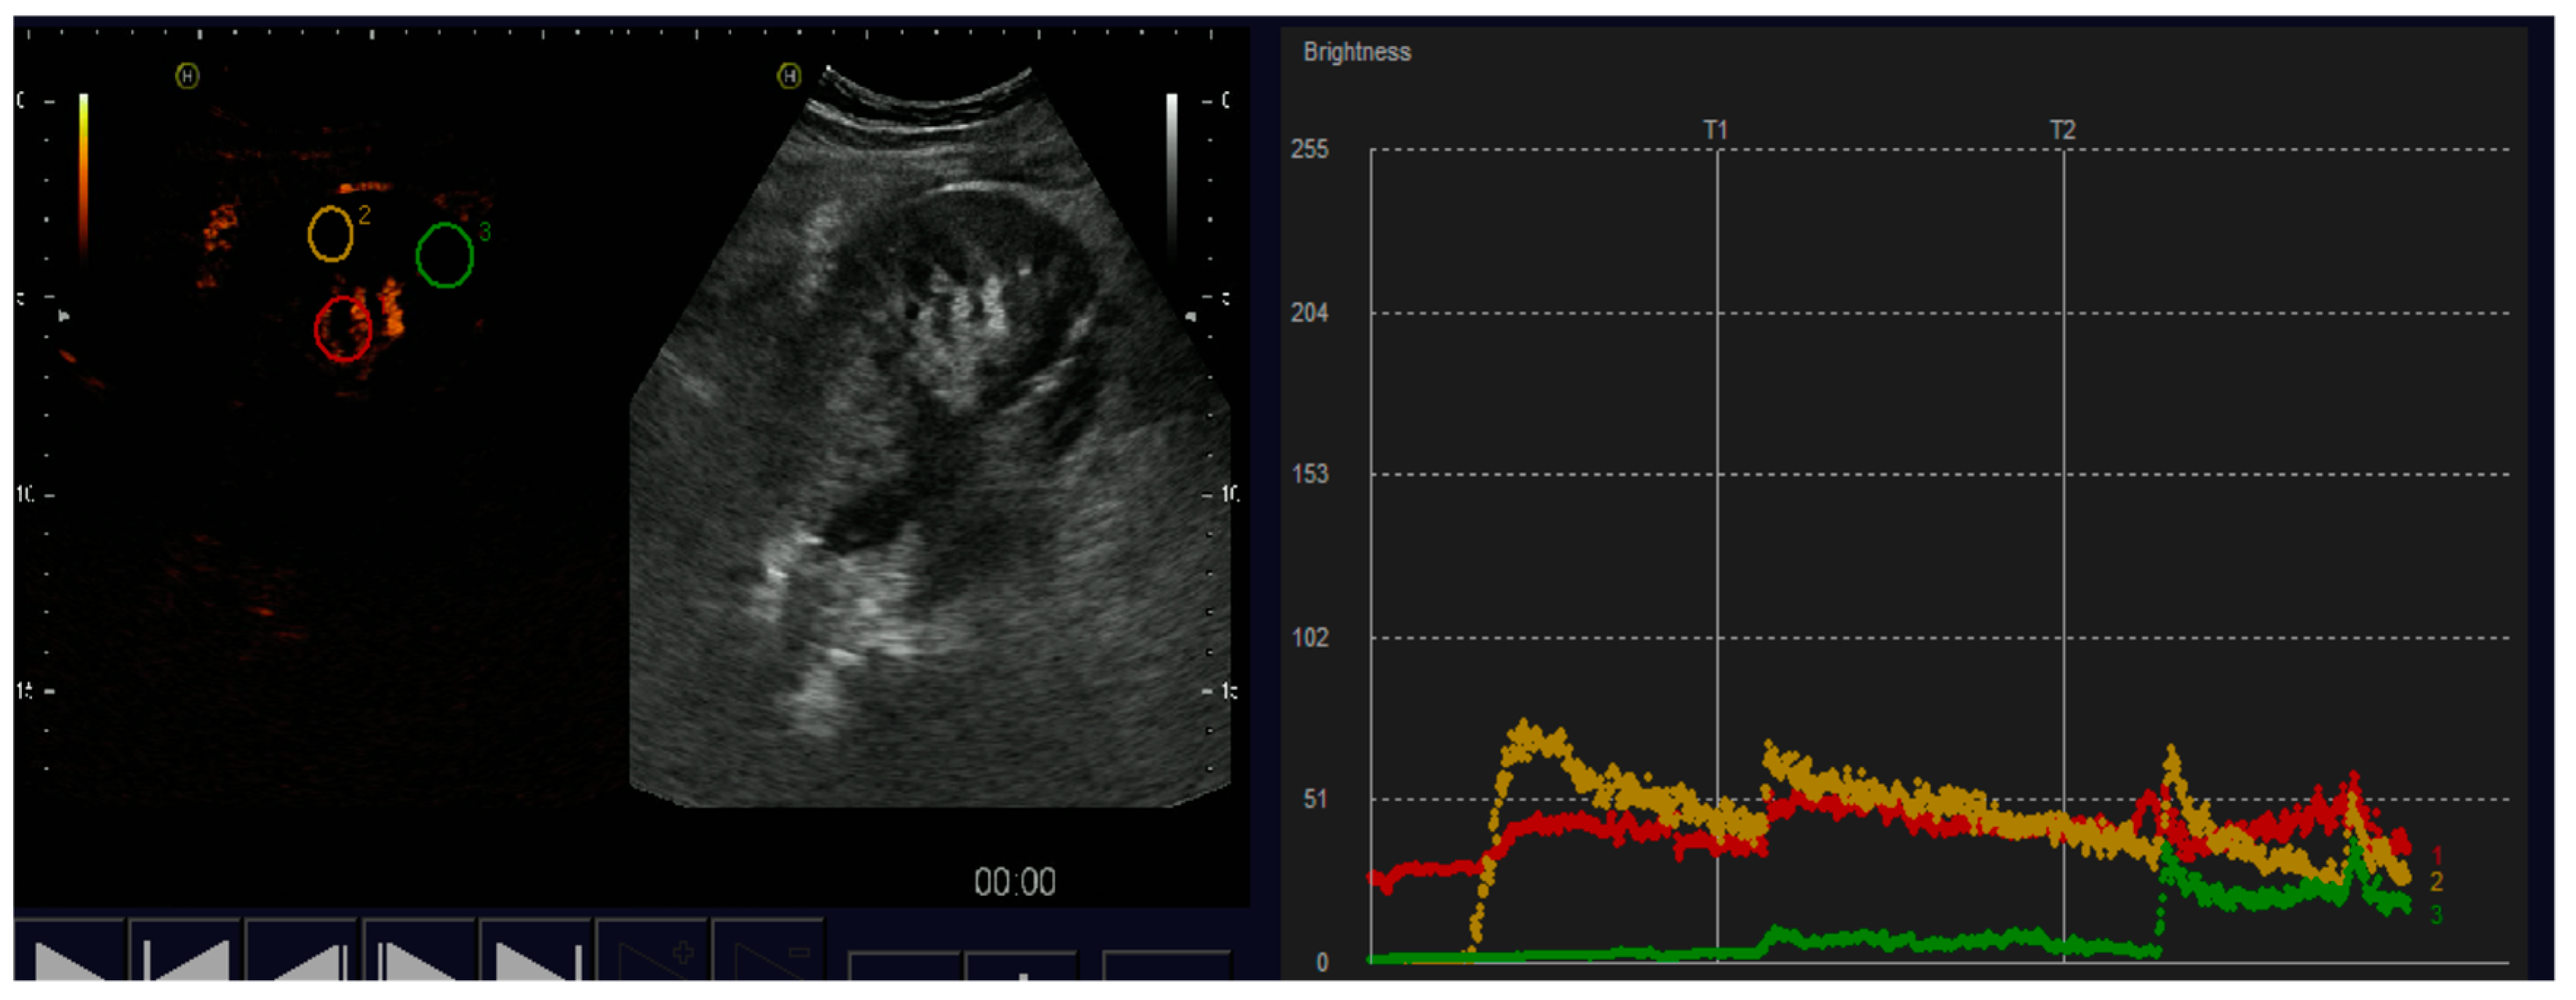

4.1.1. Arterial Thrombosis